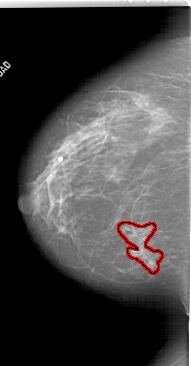

A_1788_1.LEFT_CC

LEFT_CC LINES 6211 PIXELS_PER_LINE 3241 BITS_PER_PIXEL 12 RESOLUTION 43.5 OVERLAY

FILE: A_1788_1.LEFT_CC.OVERLAY

TOTAL_ABNORMALITIES 1

ABNORMALITY 1

LESION_TYPE MASS SHAPE IRREGULAR MARGINS SPICULATED

ASSESSMENT 4

SUBTLETY 4

PATHOLOGY BENIGN

TOTAL_OUTLINES 1

BOUNDARY